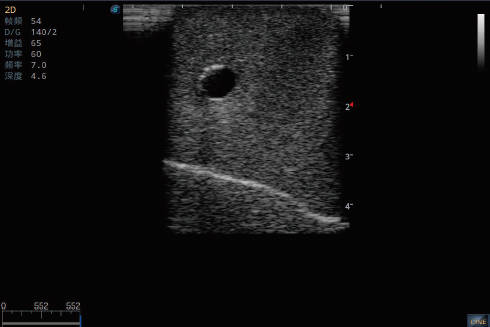

深静脉置管模型

产品型号 NO.TY1510.2

产品尺寸(mm) 700×500×160